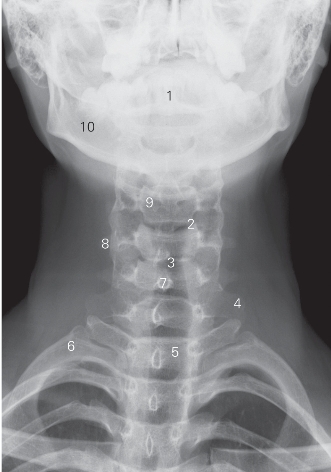

图6-1 颈椎正位DR平片

1 齿状突 odontoid 2 钩椎关节 uncovertebral joint

3 第5/6颈椎间隙 5th/6th cervical intervertebral space

4 第7颈椎横突 7th cervical transverse process

5 第1胸椎椎体 1st thoracic vertebral body 6 第1肋骨 1st rib

7 棘突 spinous process

8 第5颈椎横突 5th cervical transverse process

9 第4颈椎椎体 4th cervical vertebral body 10 下颌骨 lower jawbone